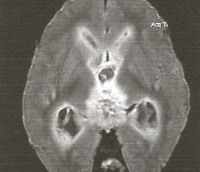

• КТ головного мозга а. Выявляет гидроцефалию, повышение плотности цереброспинальной жидкости, отёчность перивентрикулярных тканей. Обнаруженные изменения носят неспецифический характер, оцениваются в совокупности с клинической картиной, результатами анализа ликвора. Однозначно говорить о наличии вентрикулита по данным КТ можно при визуализации инородного тела в желудочке, прорыва мозгового абсцесса, посттравматического ликворного свища.